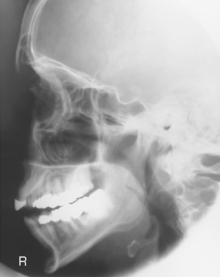

Facial Bones—Lateral*

Lateral Facial Bones

Lateral (R)

Lateral critique